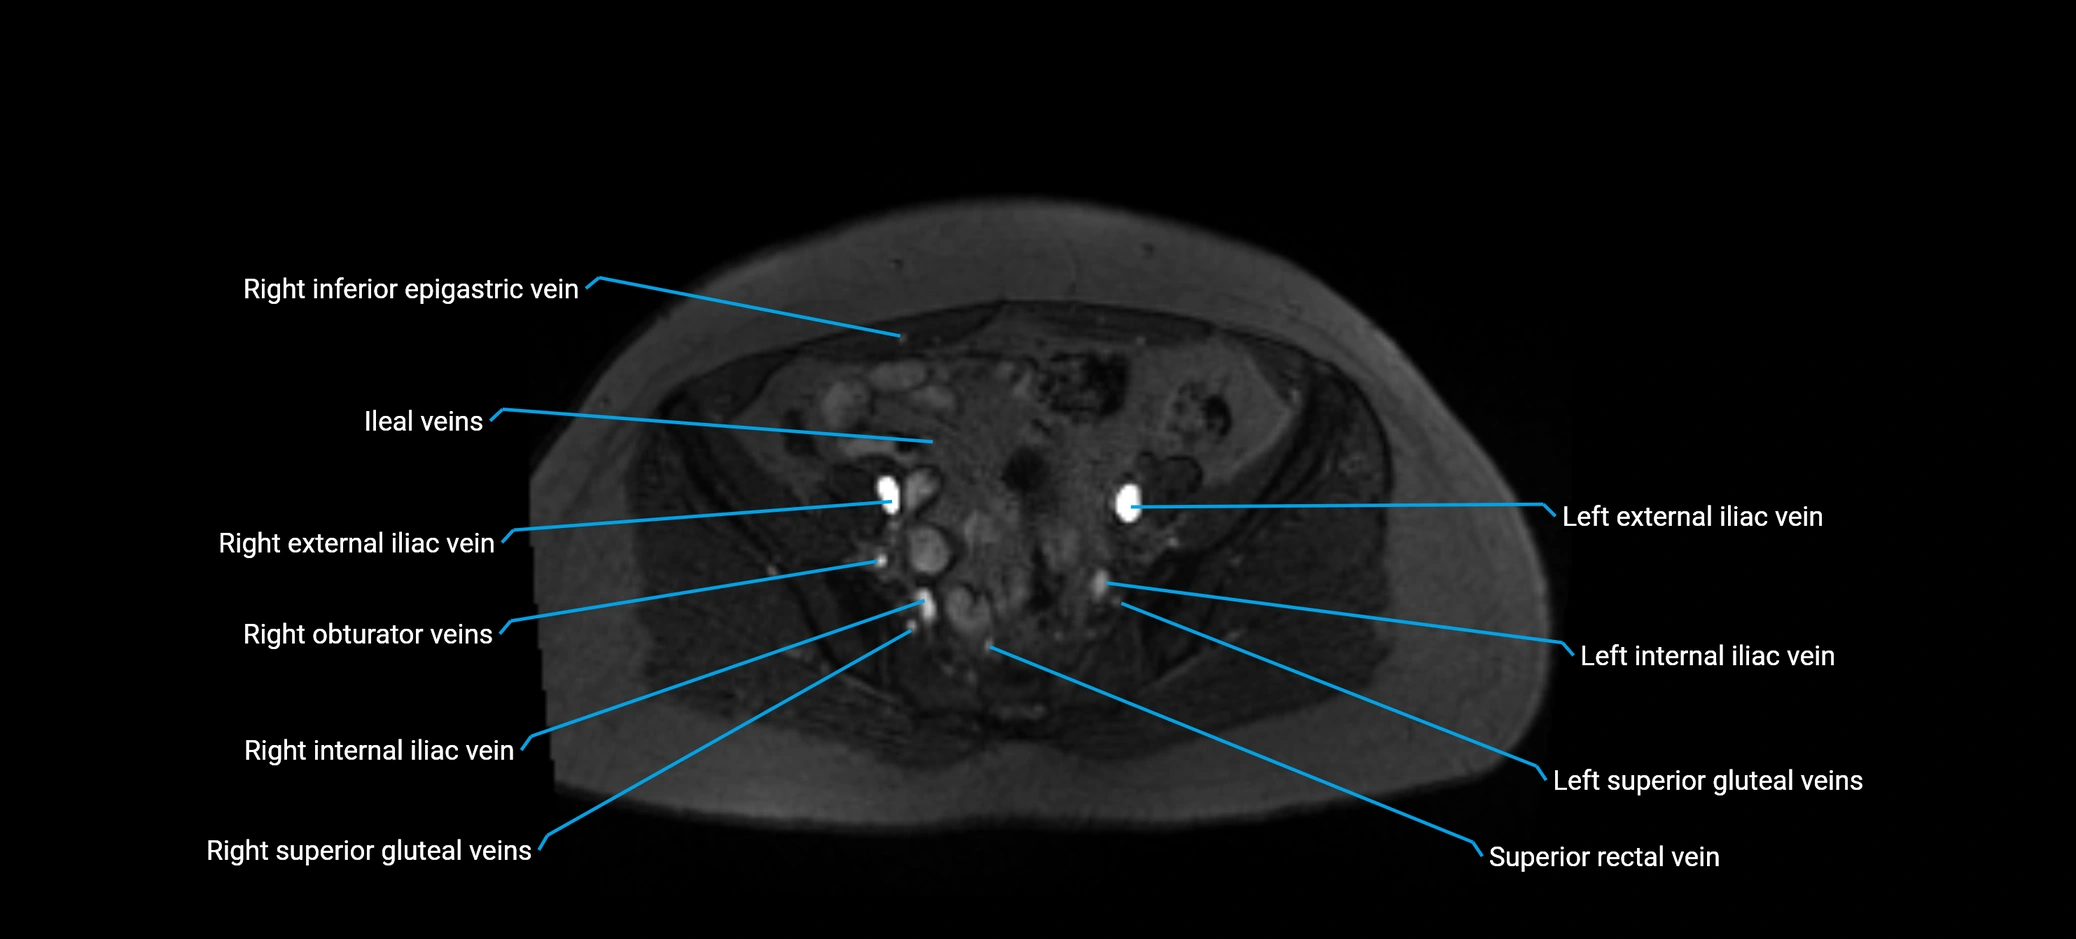

MRI image

image